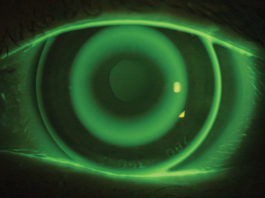

Trapianto parziale di cornea: approntata un’innovativa tecnica laser ad alta precisione

Al Bambino Gesù di Roma è stato messo a punto un approccio chirurgico evoluto, il Big-Bubble Full...